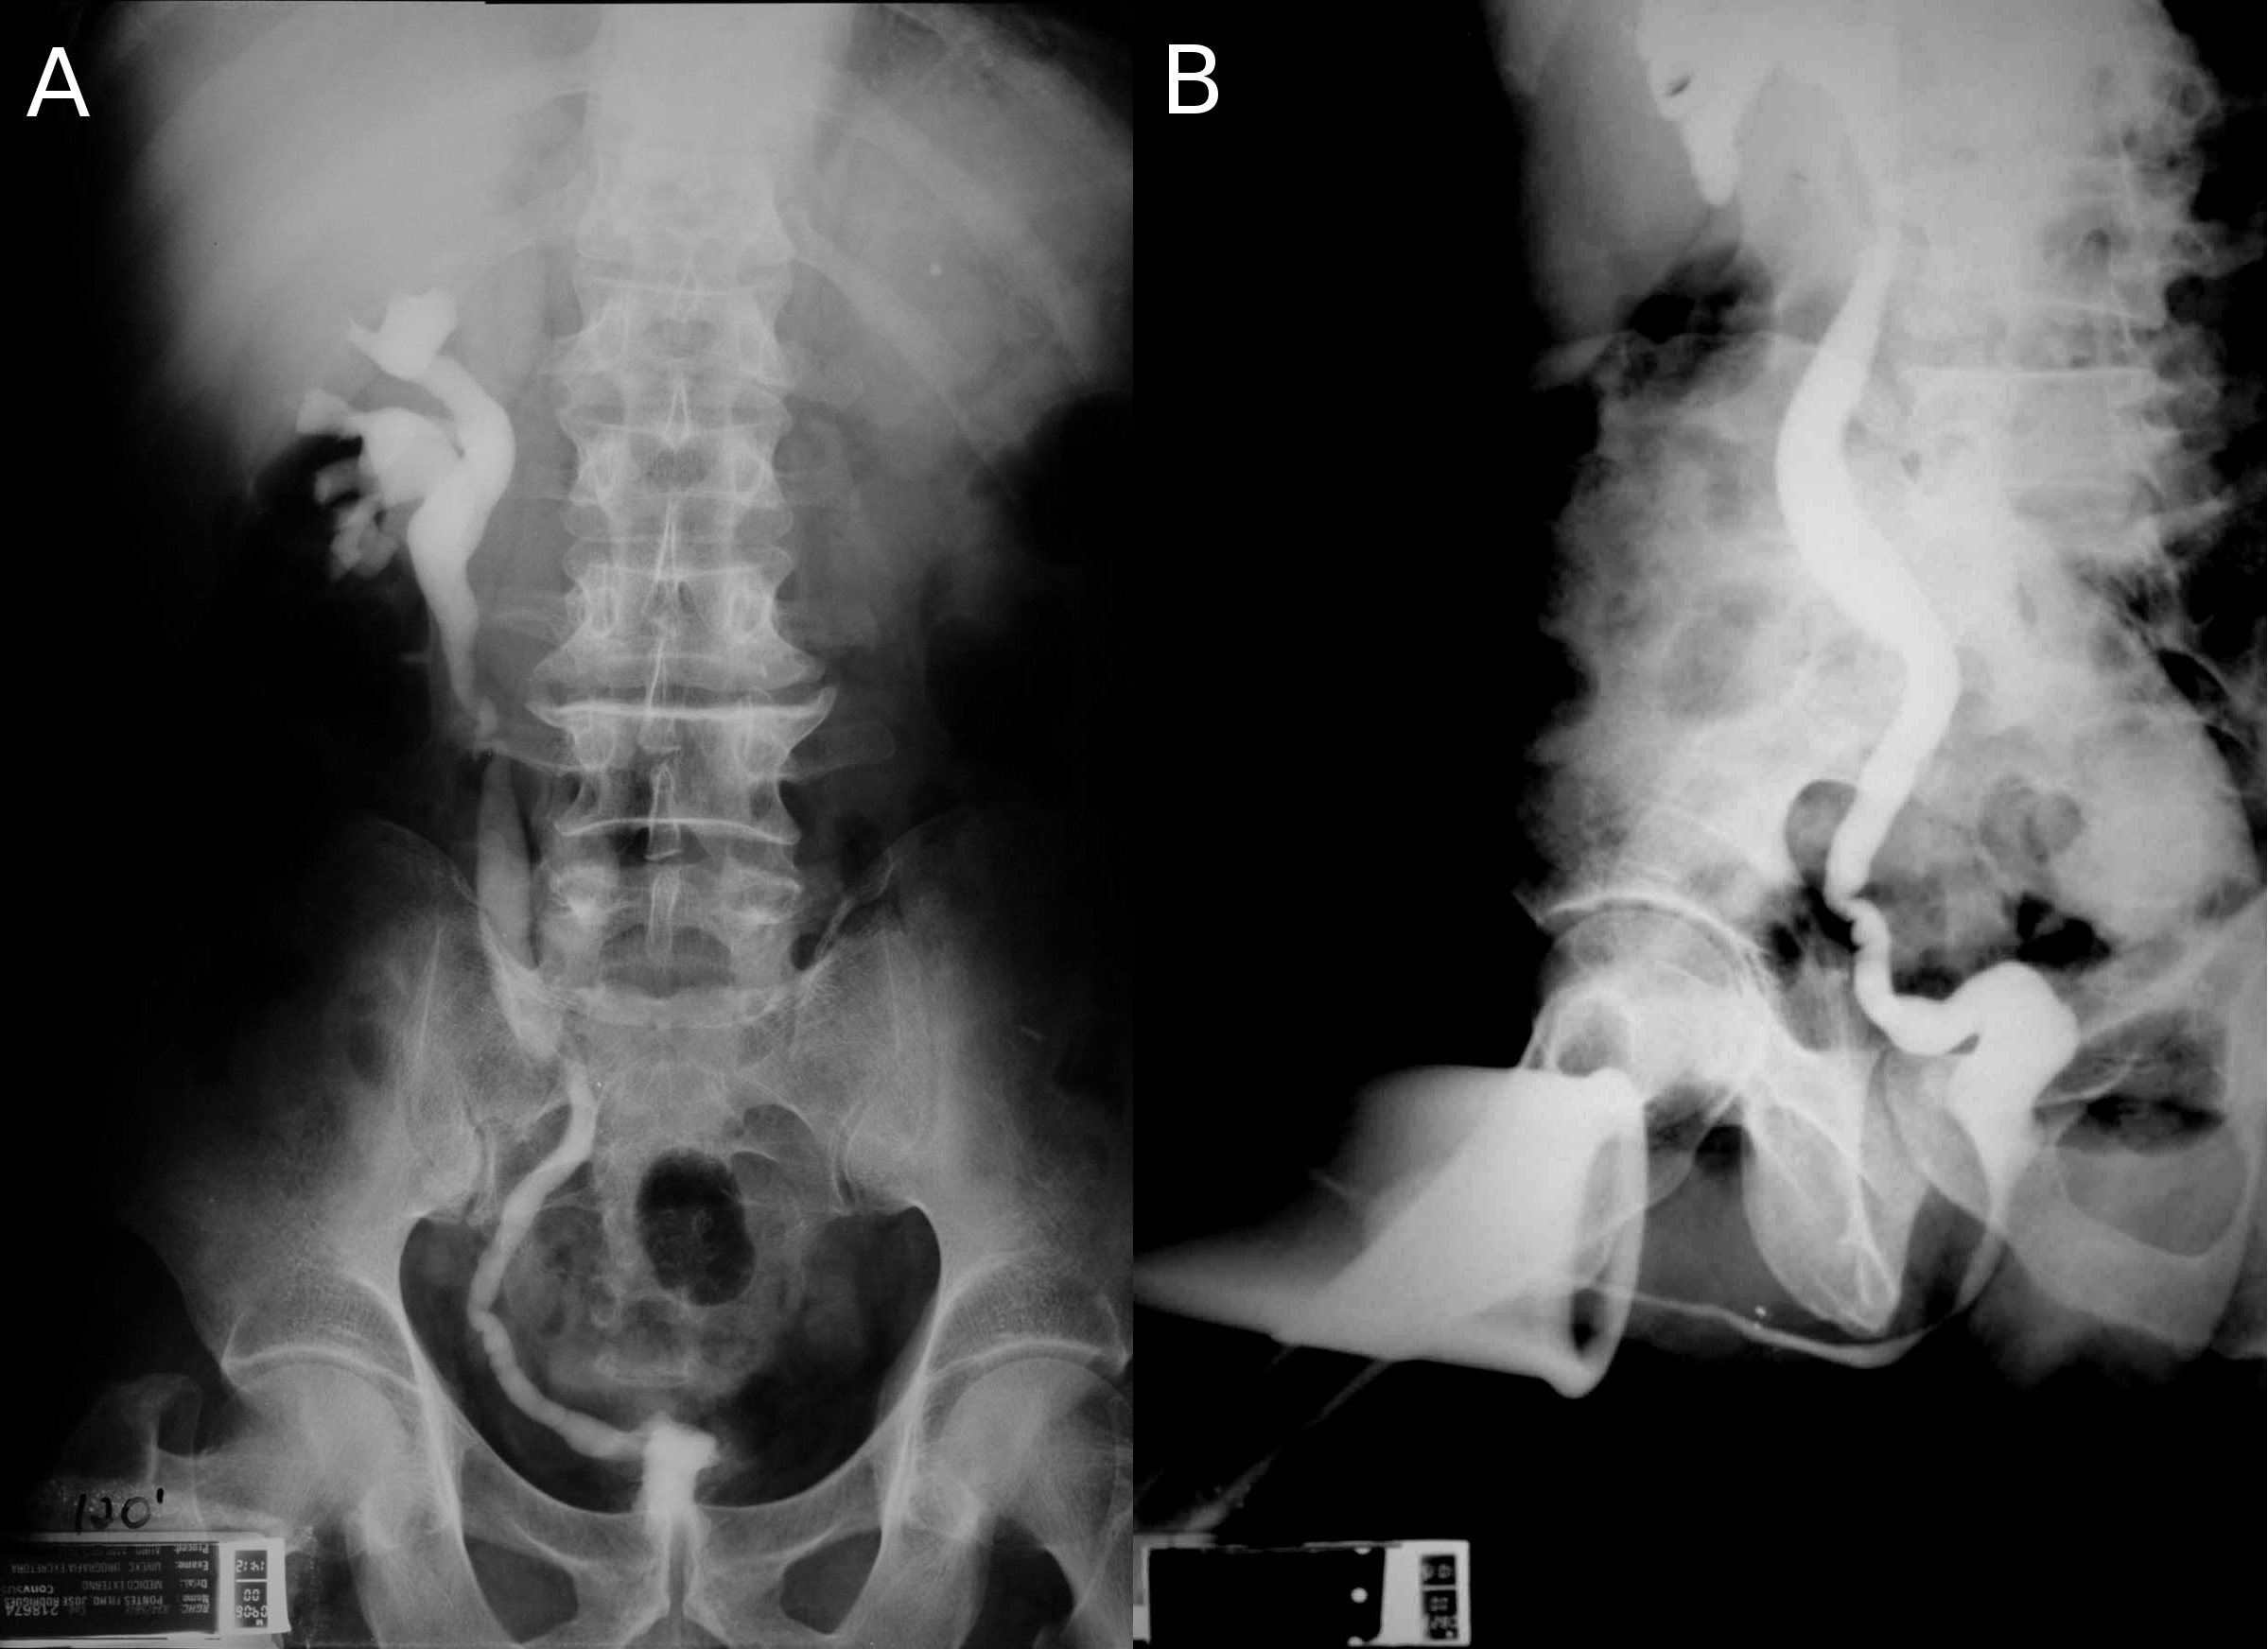

Bladder tuberculosis is secondary to kidney tuberculosis and is caused by descendent urinary dissemination. Although urogenital tuberculosis has no specific initial symptoms or radiological findings, bladder tuberculosis has a characteristic clinical and radiological finding: the contracted bladder. In a review of published series of urogenital tuberculosis, contracted bladder was found in 8.9% of urogenital tuberculosis cases, but with a difference between developed (4.0%) and developing countries (13.6%) [23]. Radiologically, the contracted bladder presents with diffuse thickening of the bladder wall, without trabeculations or diverticulas. The vesicoureteral junction is located in the lateral upper part of the bladder, and it looks like the whole bladder has contracted except for the trigone [25] (Figure 1). Clinically, the patient presents with high urinary frequency, with a voiding interval of less than 20 minutes and a bladder capacity of less than 100 ml. Sometimes incontinence develops. The presence of a contracted bladder represents an advanced stage of urogenital tuberculosis infection. There is a hypothesis based on radiographic findings that tuberculosis involvement of the urinary tract may be sequential. After unilateral renal and ureteral involvement with thickening and stenosis of the collecting system with hydronephrosis and renal parenchyma atrophy and eventually loss of function, bladder damage may follow, with diffuse thickening of the bladder wall and development of secondary vesicoureteral reflux, usually unilateral to the still unaffected kidney. High-grade reflux may lead to ureterohydronephrosis, reflux nephropathy and risk of end-stage renal failure [25]. The mechanism that vesicoureteral reflux cause hydronephrosis and kidney damage leading to terminal renal failure was described already in 1969 [26], [27]. Therefore, patients with contracted bladder might present with tuberculous kidney disease and even terminal renal failure. The typical finding is a contracted bladder with unilateral ureteral obstruction (prone to re-implantation) or a non-function (prone to nephrectomy) kidney. The other kidney is usually normal or with hydronephrosis secondary to vesicoureteral reflux [26], [27], [28], [29], [30], [31], [32], [33], [34], [35], [36] (Figure 1).